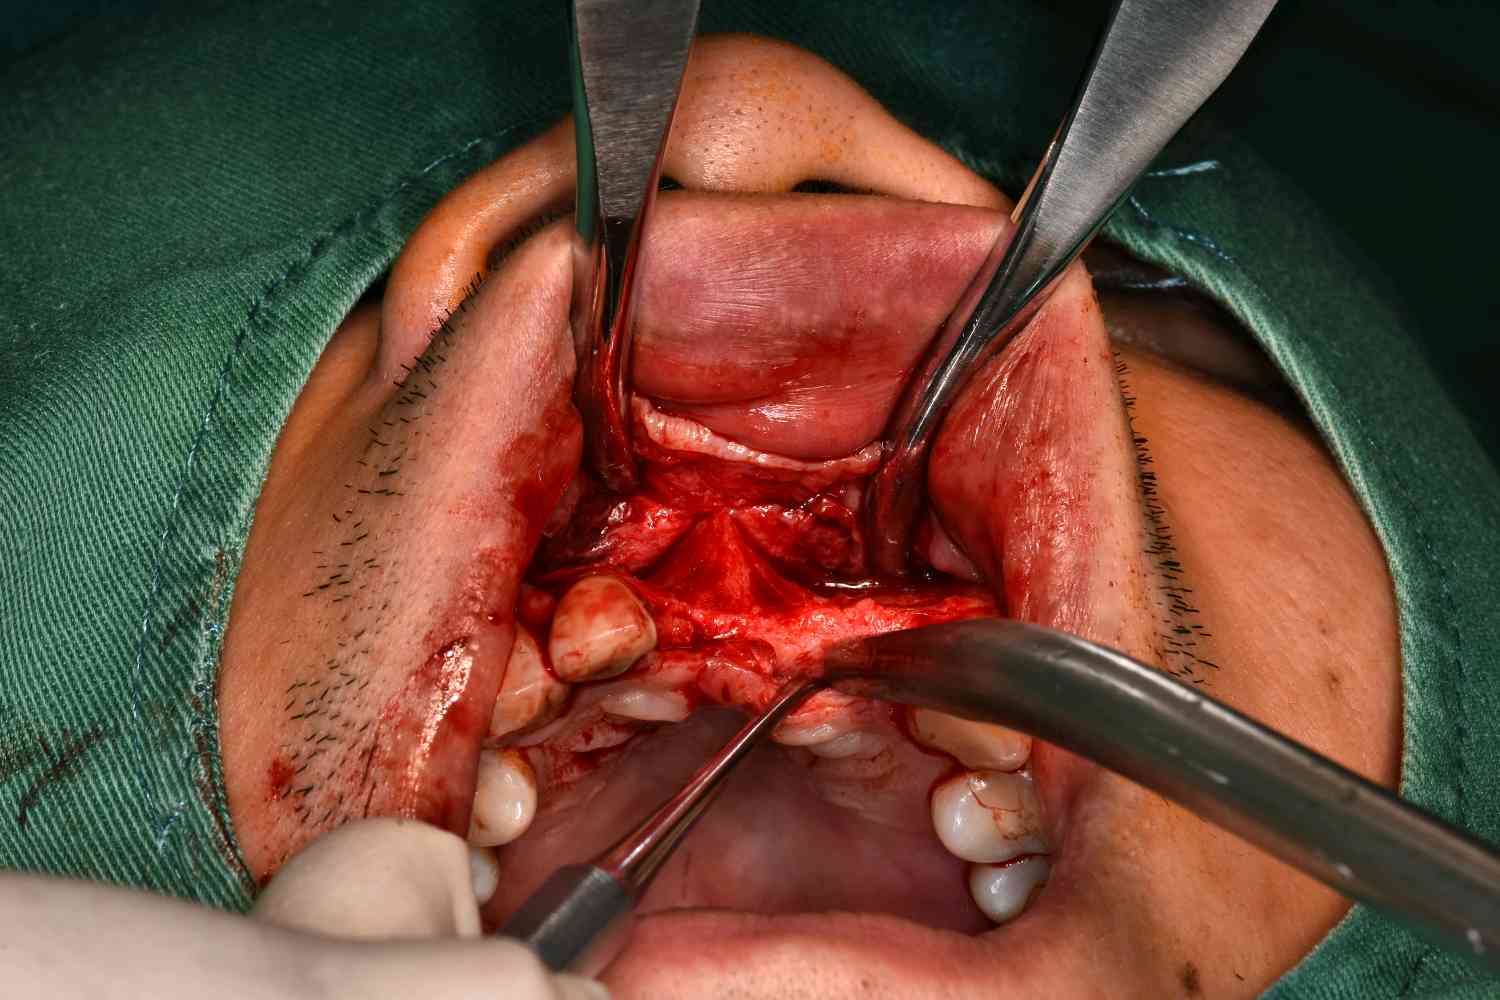

术中

图片发自160App